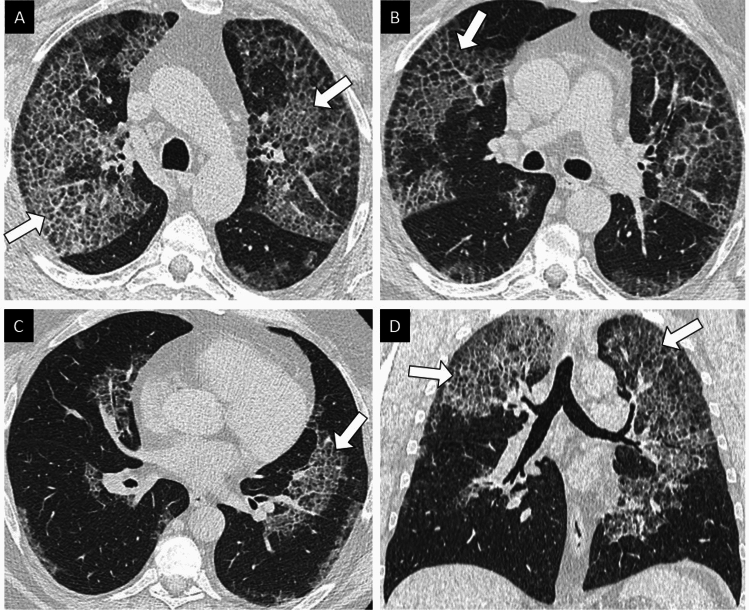

当胸部CT扫描显示“疯狂铺路”时,怀疑肺泡蛋白沉积症。支气管肺泡灌洗液呈周期性酸性席夫染色阳性,可见嗜酸性细胞外物质。通过检测患者血清中抗粒细胞-巨噬细胞集落刺激因子抗体,证实自身免疫性肺泡蛋白沉积症。历史上,自身免疫性肺泡蛋白沉积症的一线治疗方法是全肺灌洗,这只能在专家中心进行。它仍然是呼吸衰竭患者的首选治疗方法,特别是在诊断时。在最近的随机安慰剂对照研究的积极结果之后,在自身免疫性肺泡蛋白沉积症的国际指南中,现在认为补充molgramostim或sargramostim是一种吸入粒细胞-巨噬细胞集落刺激因子。利妥昔单抗和血浆置换可分别作为三线和四线治疗。晚期呼吸衰竭患者可考虑肺移植。对自身免疫性肺泡蛋白沉积症发病机制的深入了解开辟了新的治疗途径,如使用PPARγ激动剂或他汀类药物。

Pulmonary alveolar proteinosis is suspected when a "crazy paving" pattern is observed on a chest CT scan. This diagnosis is confirmed by the presence of eosinophilic extracellular material that shows positive staining with Periodic Acid Schiff on bronchoalveolar lavage samples. The autoimmune form of pulmonary alveolar proteinosis is confirmed by detecting anti-granulocyte-macrophage colony-stimulating factor antibodies in the patient's serum. The historical first-line treatment for autoimmune pulmonary alveolar proteinosis is whole lung lavage, which should only be performed in expert centers. It remains the preferred treatment for patients experiencing respiratory failure, especially at the time of diagnosis. Inhaled granulocyte-macrophage colony-stimulating factor supplementation with molgramostim or sargramostim is now considered a first-line treatment in the international guidelines for autoimmune pulmonary alveolar proteinosis, following the positive results of recent randomized placebo-controlled studies. Rituximab and plasmapheresis can be prescribed as third- and fourth-line treatments, respectively. Lung transplantation may be considered for eligible patients experiencing terminal respiratory failure. A deeper understanding of the pathogenesis of autoimmune pulmonary alveolar proteinosis has opened up new therapeutic avenues, such as the use of PPARγ agonists or statins.